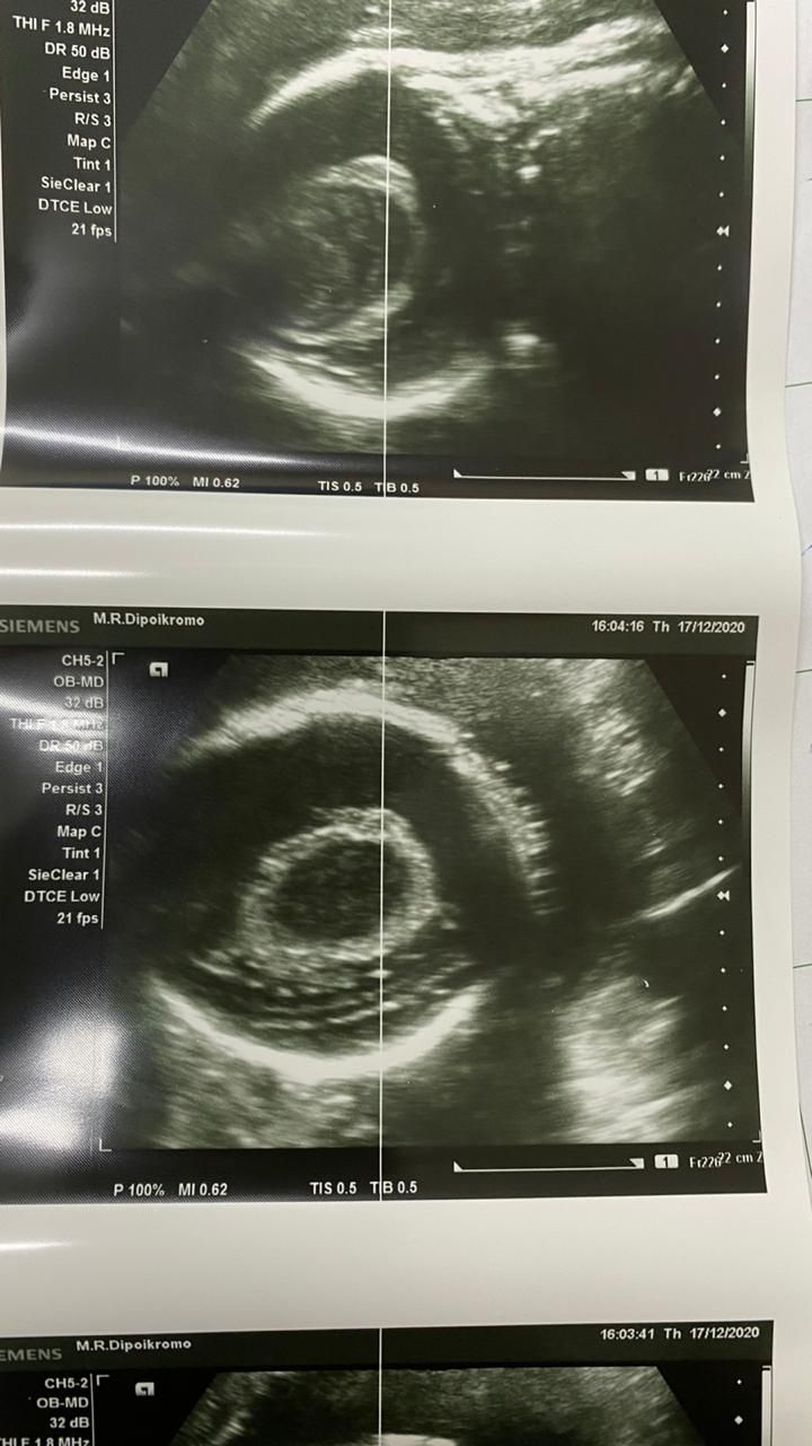

Head circumference echography of 32 week old fetus.

Head circumference echography of 32 week fetus. Seen in the echo presumably midline shifting. And we think it's a plexus choroidalis cyst. However we are not sure. Kindly leave a suggestion and your explanation in the comments. Greetings, Jay